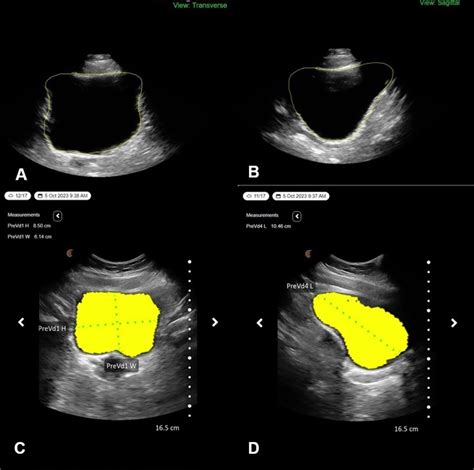

Ultrasound imaging is one of the most commonly used methods to calculate bladder volume. This non-invasive technique uses sound waves to create images of the bladder, allowing healthcare providers to measure its dimensions accurately. The formula commonly used to estimate bladder volume from ultrasound measurements is:

Volume = (Length × Width × Height) × 0.52

Here’s a step-by-step guide to using ultrasound imaging to calculate bladder volume:

• Position the patient in a supine or semi-recumbent position.

• Apply ultrasound gel to the lower abdomen.

• Use a transabdominal ultrasound probe to visualize the bladder.

• Measure the length, width, and height of the bladder in centimeters.

• Apply the formula to calculate the bladder volume.

Bladder Scanning Devices

Bladder scanning devices are portable, non-invasive tools designed to calculate bladder volume quickly and easily. These devices use ultrasound technology to estimate bladder volume without the need for a full ultrasound machine. They are particularly useful in clinical settings where rapid assessments are required.

Here’s how to use a bladder scanning device to calculate bladder volume:

• Position the patient comfortably.

• Place the scanning probe on the gel-covered area.

• Activate the device to capture the bladder image.

• Read the volume measurement displayed on the device.